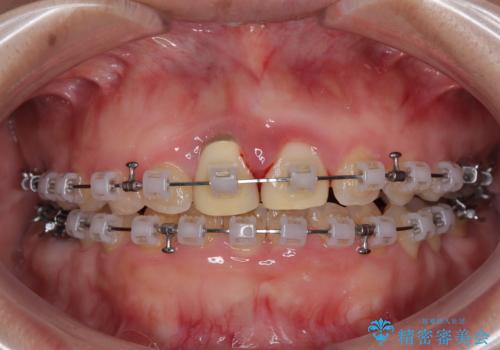

マウスピース装着は煩わしいとのことで、表側のワイヤー装置にて矯正治療を行うこととしました。

前歯のクラウンは変色が顕著なため、矯正治療後にオールセラミッククラウンによる補綴治療を行うこととしました。